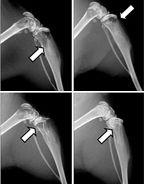

Representative x-ray images from the hind limbs of mice. Arrows indicate osteolytic lesions. Source: Dunn LK, et al.

PLoS ONE

4(9), 2009, e6896